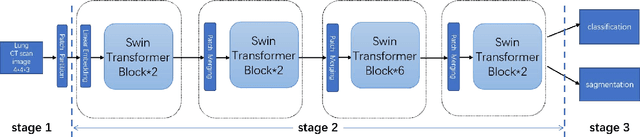

With the development of computer technology, various models have emerged in artificial intelligence. The transformer model has been applied to the field of computer vision (CV) after its success in natural language processing (NLP). Radiologists continue to face multiple challenges in today's rapidly evolving medical field, such as increased workload and increased diagnostic demands. Although there are some conventional methods for lung cancer detection before, their accuracy still needs to be improved, especially in realistic diagnostic scenarios. This paper creatively proposes a segmentation method based on efficient transformer and applies it to medical image analysis. The algorithm completes the task of lung cancer classification and segmentation by analyzing lung cancer data, and aims to provide efficient technical support for medical staff. In addition, we evaluated and compared the results in various aspects. For the classification mission, the max accuracy of Swin-T by regular training and Swin-B in two resolutions by pre-training can be up to 82.3%. For the segmentation mission, we use pre-training to help the model improve the accuracy of our experiments. The accuracy of the three models reaches over 95%. The experiments demonstrate that the algorithm can be well applied to lung cancer classification and segmentation missions.